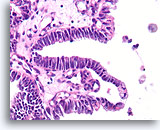

Papillair neoplasma, Borst FNA, Celblok.

Een kleine vergroting van de residuele naaldspoeling van de patiënt in afbeelding 39-42 toont een duidelijk papillaire architectuur. Let op de gelijksoortigheid van de ductale populatie in dit hele veld. Dit monotone patroon duidt meer op een papillair carcinoom dan een papilloom.

40X

Papillair neoplasma, Borst FNA, Celblok.

Een kleine vergroting van de residuele naaldspoeling van de patiënt in afbeelding 39-42 toont een duidelijk papillaire architectuur. Let op de gelijksoortigheid van de ductale populatie in dit hele veld. Dit monotone patroon duidt meer op een papillair carcinoom dan een papilloom.

40X

Papillair carcinoom, Borst FNA, Celblok.

Sterkere vergroting van de patiënt uit afbeelding 39-43 toont een fibrovasculaire kern (open pijl) en een cribriform gebied dat consistent is met een papillair carcinoom (pijl).

10X

Papillair carcinoom, Borst FNA, Celblok.

Sterkere vergroting van de patiënt uit afbeelding 39-43 toont een fibrovasculaire kern (open pijl) en een cribriform gebied dat consistent is met een papillair carcinoom (pijl).

10X

Papillair carcinoom, Borst FNA, Celblok.

Een ander cribriform gebied (pijl) en een fibrovasculaire kern (open pijl) kunnen gemakkelijk worden onderscheiden.

10X

Papillair carcinoom, Borst FNA, Celblok.

Een ander cribriform gebied (pijl) en een fibrovasculaire kern (open pijl) kunnen gemakkelijk worden onderscheiden.

10X